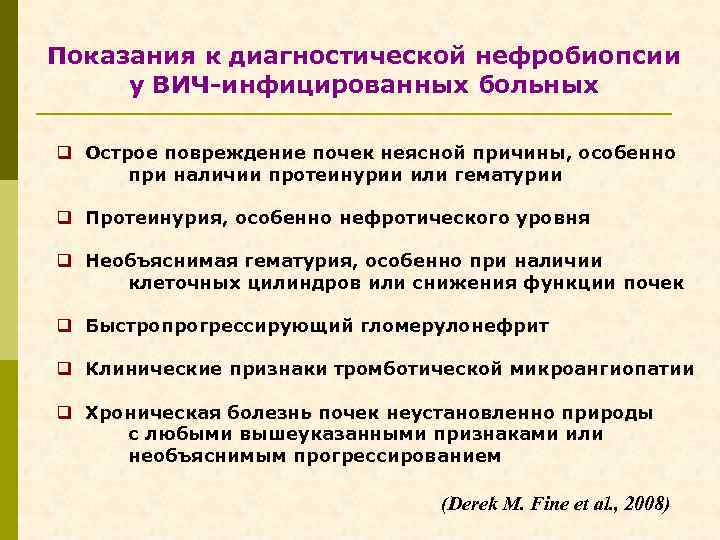

Нефрологические аспекты обследования ВИЧ-инфицированных больных Б. Показания к нефробиопсии p При наличии признаков поражения почек (протеинурия, снижение СКФ) антиретровирусная терапия назначается без знания морфологического диагноза. p Нефробиопсия выполняется в том случае, если по истечении 3 -х месяцев не наблюдается улучшения почечных функций. p Протеинурия > 1 г/сут. , СКФ < 90 мл/мин. p Микроальбуминурия (? ? )

Показания к диагностической нефробиопсии у ВИЧ-инфицированных больных q Острое повреждение почек неясной причины, особенно при наличии протеинурии или гематурии q Протеинурия, особенно нефротического уровня q Необъяснимая гематурия, особенно при наличии клеточных цилиндров или снижения функции почек q Быстропрогрессирующий гломерулонефрит q Клинические признаки тромботической микроангиопатии q Хроническая болезнь почек неустановленно природы с любыми вышеуказанными признаками или необъяснимым прогрессированием (Derek M. Fine et al. , 2008)